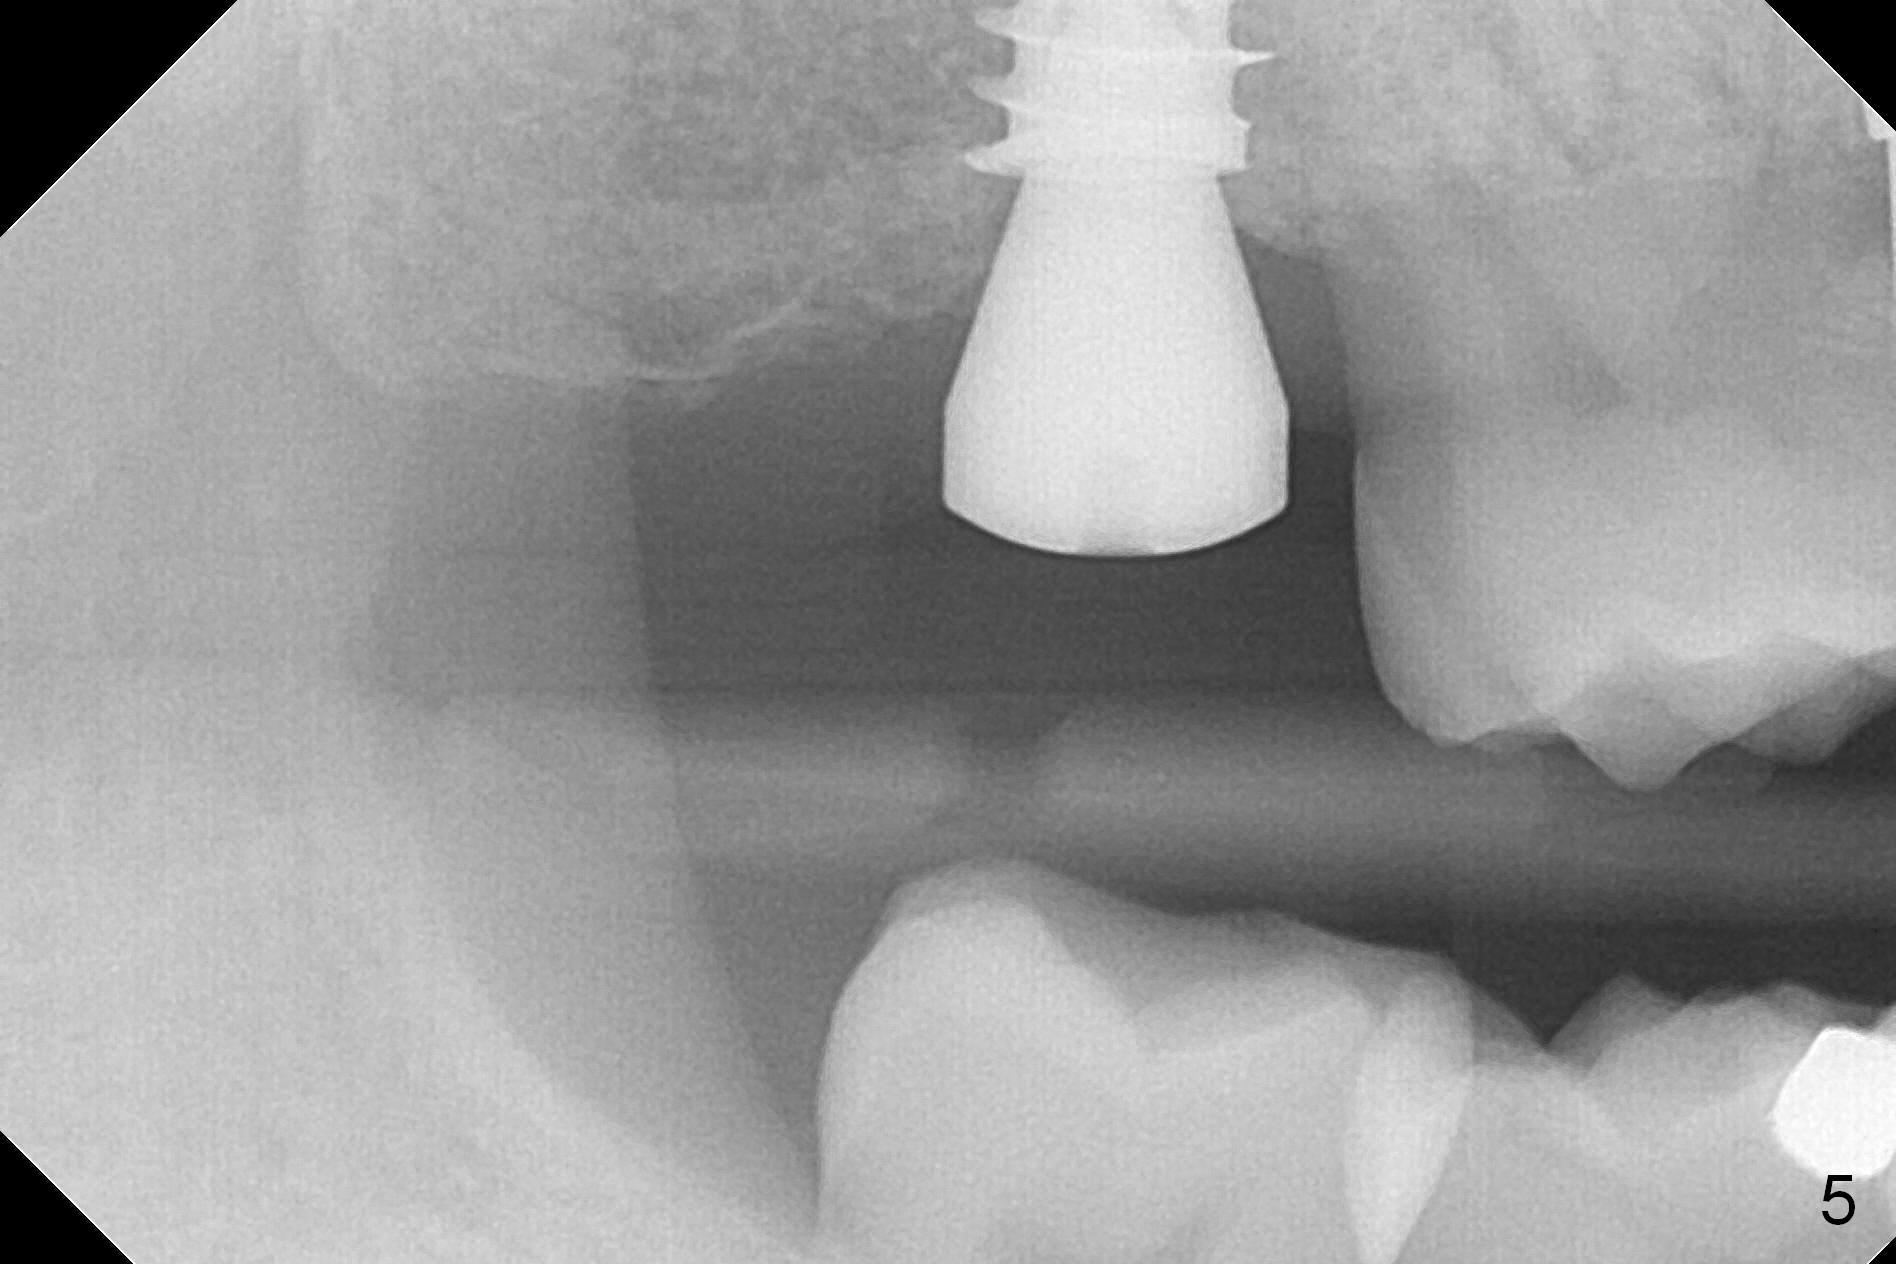

Since the ridge at the site of #2 is wide (Fig.1), Magic Split is used for access and bone density determination. In fact it enters for 9 mm (gingival level), followed by Magic Expander (ME) 3 mm (Fig.2 *). The center of the latter is 3.9 mm from the distal surface of the tooth #3. Lindamann bur is used to move the osteotomy distal, followed by sequential use of MEs until 4.3 mm one. When a 5x9 mm dummy implant is placed, its center is somewhat mesial (Fig.3 brown line). What needs to be done is change the trajectory to the red line so that the coronal end of the definitive implant (5.5x9 mm) will be placed evenly subcrestal (Fig.4,5). It is what happens, although slightly too subcrestal. Insertion torque is <35 Ncm; a 6x4 mm healing abutment is placed. ME 4.8 mm has to be tapped for 13 mm from gingival margin in order to let the implant penetrate the sinus floor. IBS implants seem to lack self tapping ability. Its tap drills should possess this capacity. Allograft/autogenous bone (harvested from dummy implant) is placed prior to implantation. The patient returns for impression 6 months postop (Fig.6,7; #4). A 5x4(3) mm abutment is placed; its height is reduced as well as the opposing supraerupted tooth (Fig.5) prior to impression.